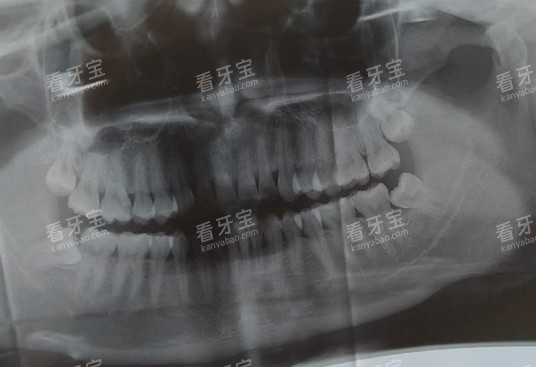

要是半口牙都缺了,也有专门的方案:半口半固定种植牙 26000 元起,All-on-4 半口种植牙 40000 元起,不用一颗一颗种,能省不少时间和费用。种植前会用口腔 CT 扫描,把牙槽骨的情况看得清清楚楚,医生再制定方案,让人心里有底。

接待我的是秦志远医生,他先给我拍了 CT,把牙槽骨的情况展示给我看,说我的条件可以种,还推荐了韩国登腾的种植体,价格 2980 元起,比我之前问的几家都便宜。